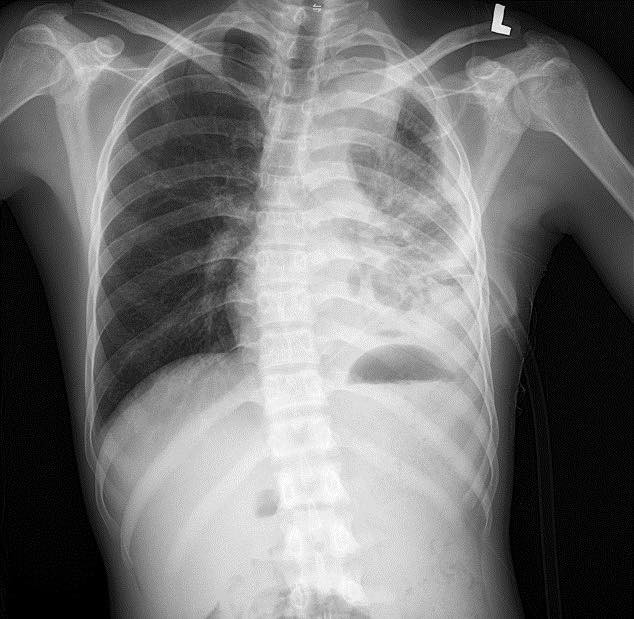

Tổn thương phổi trên phim chụp - Ảnh BVCC

Kết quả xét nghiệm máu cho thấy tình trạng nhiễm trùng nặng với chỉ số bạch cầu (WBC) lên tới 64.8 G/L, chỉ số CRP cao 263.6 mg/dL. Với hệ thống chẩn đoán hình ảnh hiện đại, các bác sĩ ghi nhận: Đông đặc nhu mô thùy dưới phổi trái, tràn dịch màng phổi trái lượng nhiều, tràn khí màng phổi trái, phổi trái bị xẹp thụ động, đẩy lệch trung thất sang phải.